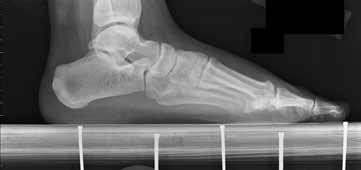

A 28-year-old male sustained a displaced talar neck fracture and underwent open reduction and internal fixation.

Six weeks postoperatively, a subchondral radiolucent band is seen in the talar dome on the AP mortise radiograph. What does this radiographic finding indicate?

Explanation

Hawkins sign is a subchondral radiolucent band seen in the talar dome 6 to 8 weeks after a talus fracture. It represents subchondral osteopenia secondary to disuse atrophy. Because bone resorption requires an active blood supply, the presence of a Hawkins sign is a highly reliable indicator that the talar body has intact vascularity and that avascular necrosis (AVN) is unlikely.